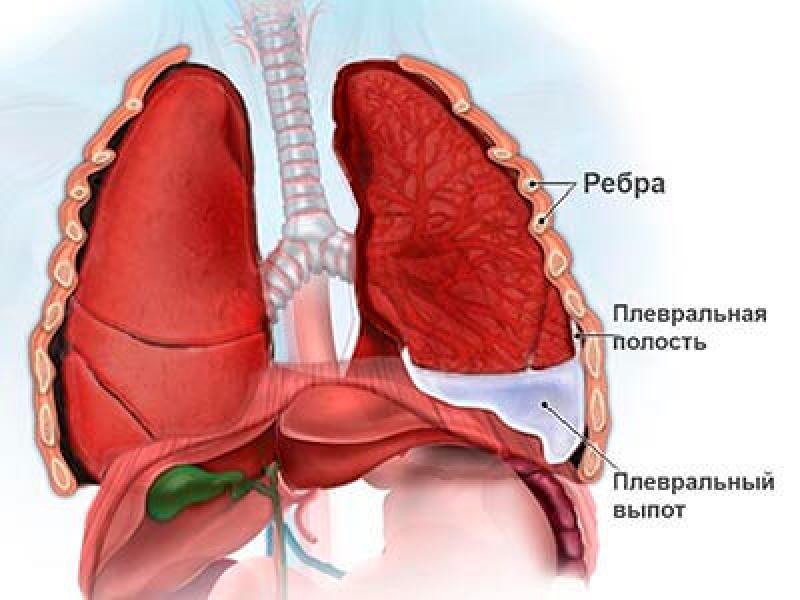

Анатомия межплеврального пространства